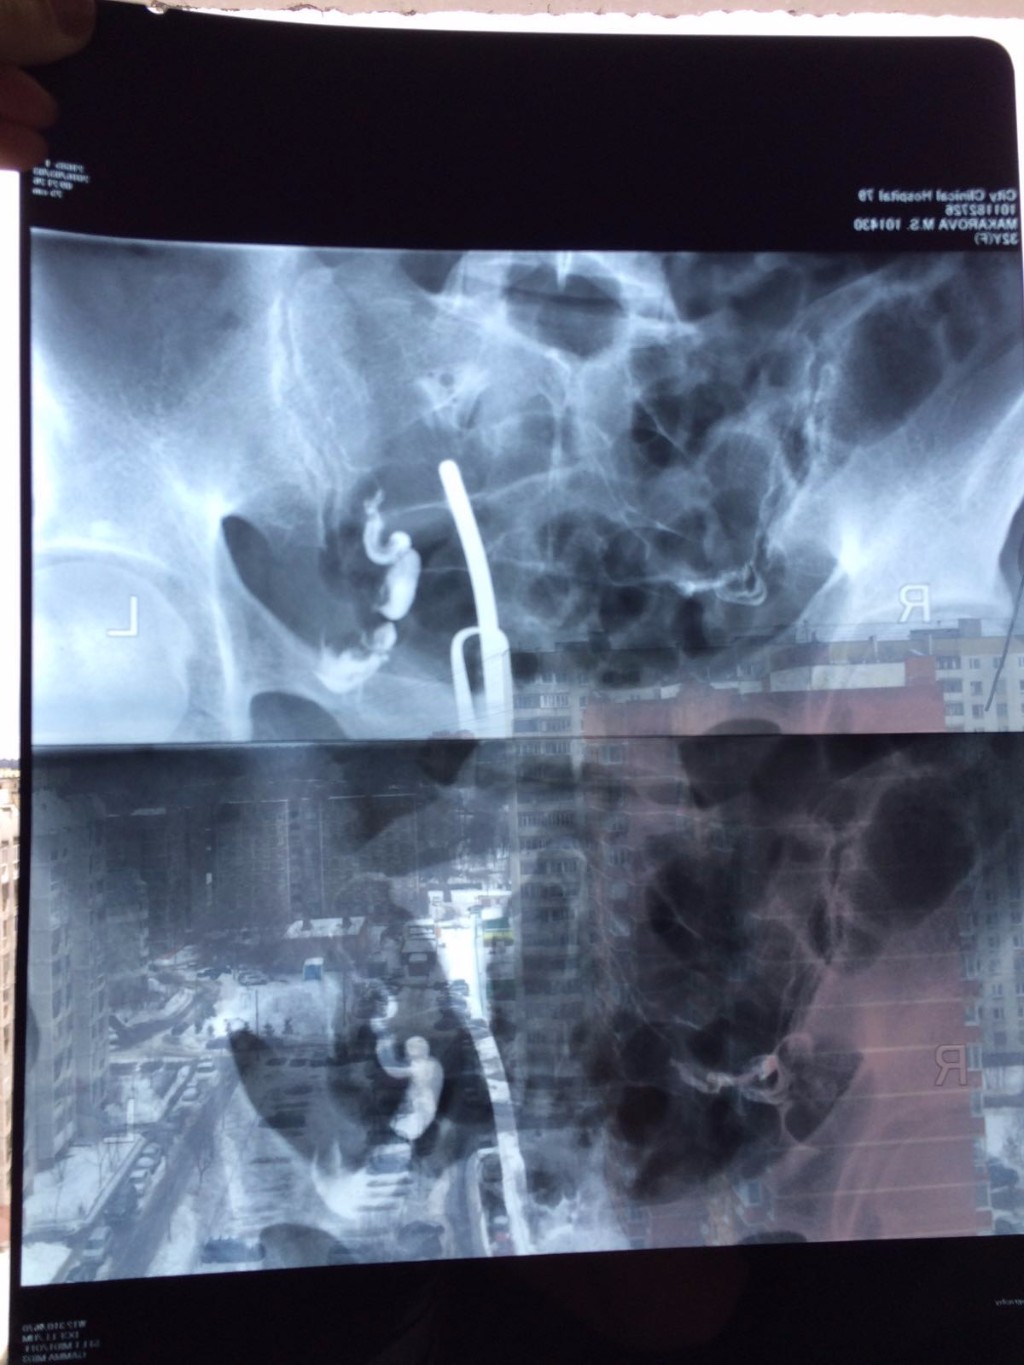

Медицинские снимки: Проходимость маточных труб